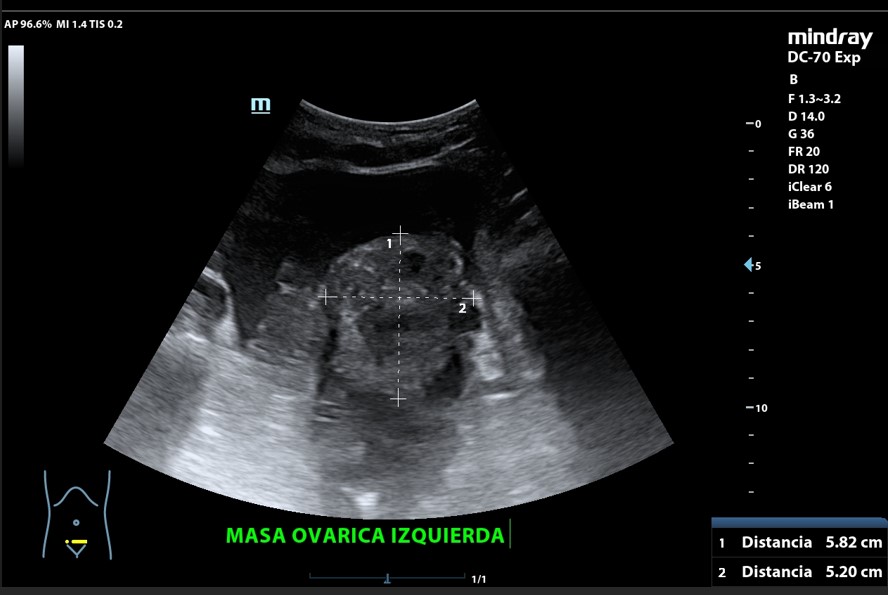

Presencia de 2 masas pélvicas bien delimitadas heterogéneas que captan Doppler, una de 5 cm de diámetro y otra ovalada de 10 cm de longitud. Líquido ascítico peritoneal, que también se observa alrededor del bazo y en espacio de Morrison. Derrame pleural derecho.

Tumoración ovárica bilateral.